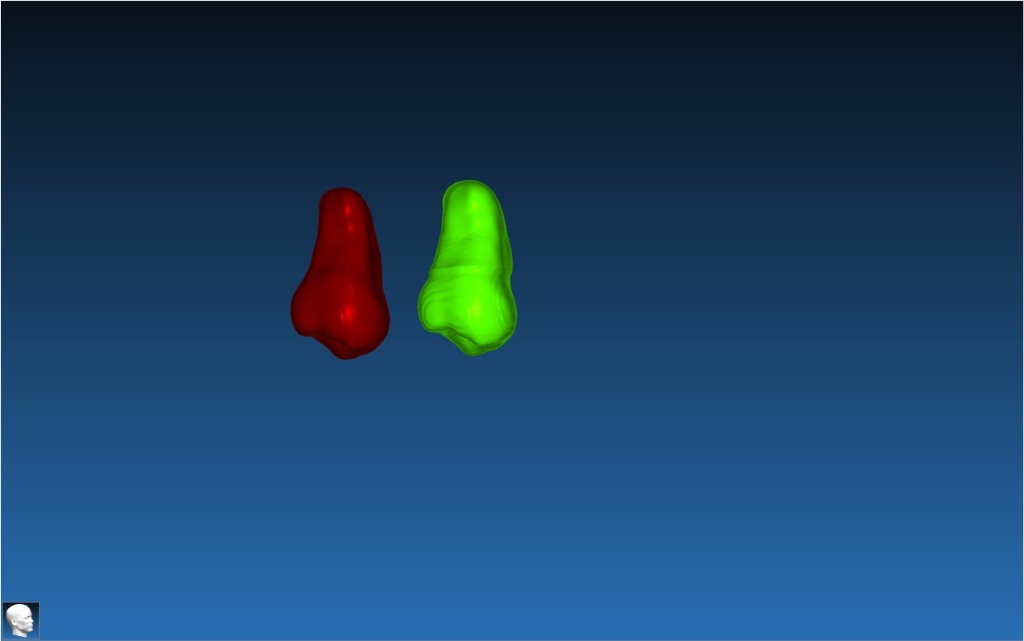

Autotransplant Template

3D replica of the donor tooth used for accurate recipient site preparation in dental autotransplantation.